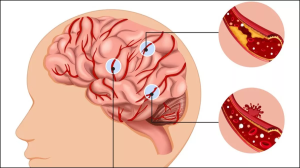

मिनी स्ट्रोक के क्या हैं लक्षण, क्या ये आने वाले स्ट्रोक की चेतावनी है, जानिए कैसे करें पहचान

अनियमित लाइफस्टाइल और खान-पान में गड़बड़ी के कारण मिनी स्ट्रोक का खतरा बढ़ जाता है। मिनी स्ट्रोक कई बार जानलेवा स्ट्रोक की चेतावनी के रूप में आता है। जिसका समय रहते इलाज कराना जरूरी है। जान लें मिनी स्ट्रोक के क्या हैं लक्षण?स्ट्रोक बेहद खतरनाक